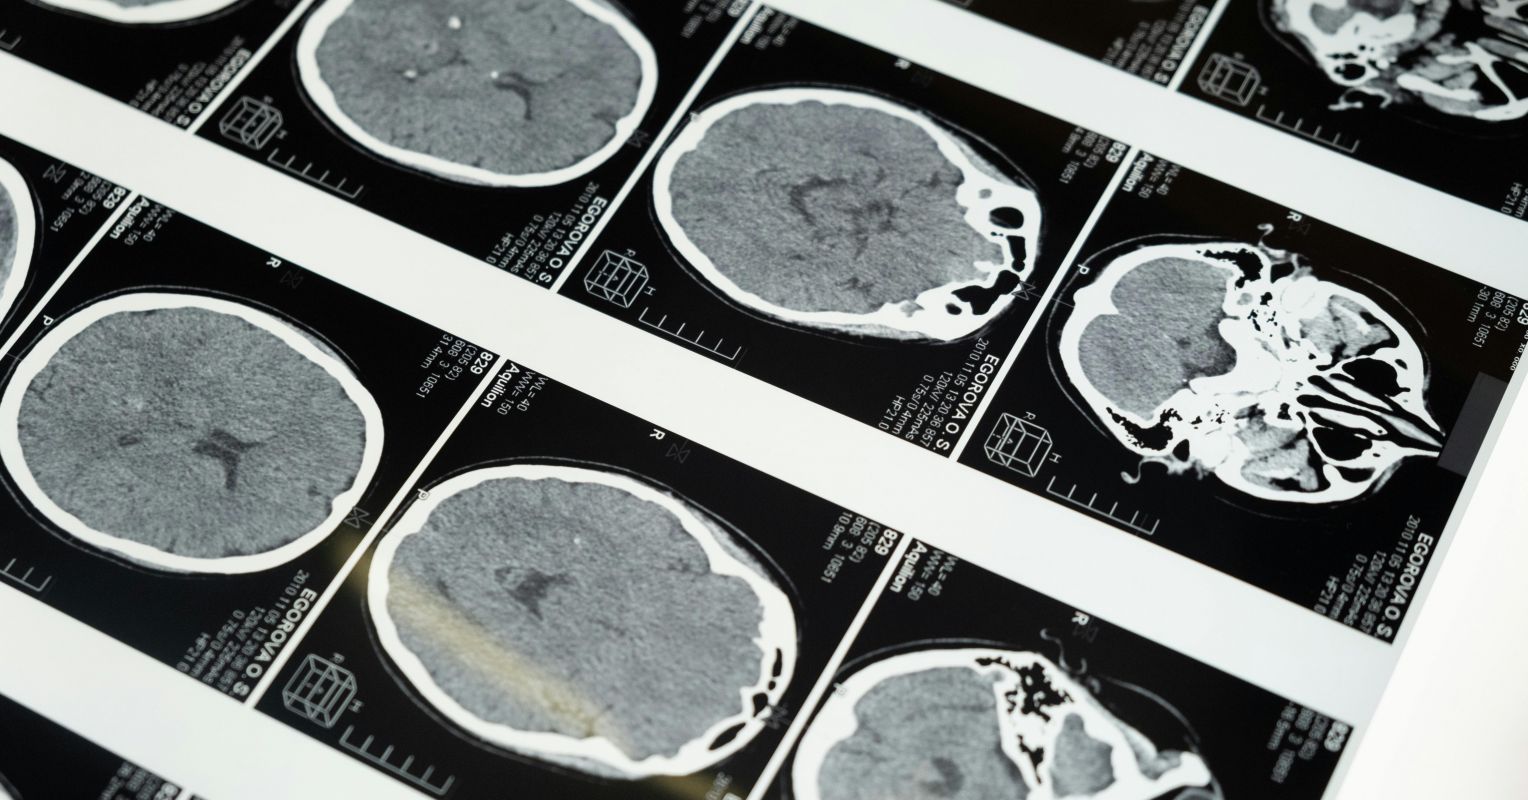

Dopamine regulates reward, focus, calm, and effort and is released when something is interesting or rewarding. Dopamine is required for executive functions; rewarding activity produces dopamine that is spent to operate those functions. Adequate dopamine produces satisfaction, focus, calmness, and stillness, while inadequate signalling produces boredom, irritability, restlessness, attentional shifting, and searching for stimulation. Structural brain differences in corpus callosum, cerebellum, basal ganglia, and reduced white matter volumes have been observed in ADHD. Genetic variants of dopamine receptors (including D2, D4, and D5) reduce dopamine signal detection, so reduced signalling strength causes a higher need for novelty to feel engaged and settled.